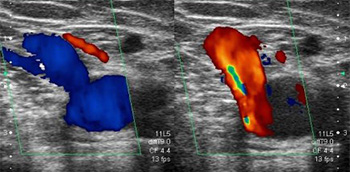

Capítulo 2. Insuficiencia venosa crónica. Screening de varices